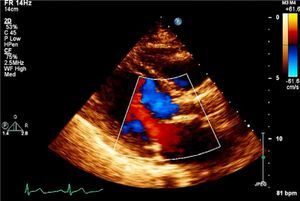

Case reportAn 83-year-old woman, with a history of hypertension (controlled), dyslipidemia, stage III chronic renal failure (creatinine clearance 45ml/min) and chronic anemia (baseline hemoglobin 11g/dl), underwent aortic valve replacement surgery in 2004 with implantation of a 21-mm Mitroflow bioprosthesis (Sorin Group Canada Inc., Burnaby, BC, Canada). She presented with progressively worsening heart failure in New York Heart Association (NYHA) functional class III. The electrocardiogram showed sinus rhythm and no relevant alterations. Transthoracic echocardiography revealed signs of aortic bioprosthesis degeneration, resulting in important valve regurgitation that was difficult to quantify but without significant limitation of valve opening. Other valve structures showed no significant morphological or functional abnormalities and there were no signs of pulmonary hypertension. The left ventricle was of normal size, with preserved global systolic function. Transesophageal echocardiography was performed to characterize prosthetic dysfunction, and showed moderately thickened aortic cuspids and reasonable systolic opening, but central malcoaptation that resulted in two regurgitant jets, one of which was directed anteriorly next to the ventricular septum, moderate to severe (grade III/IV) (Figure 1A). Subsequent cardiac catheterization confirmed significant aortic regurgitation (3+/4+) and excluded significant coronary disease (Figure 1B).